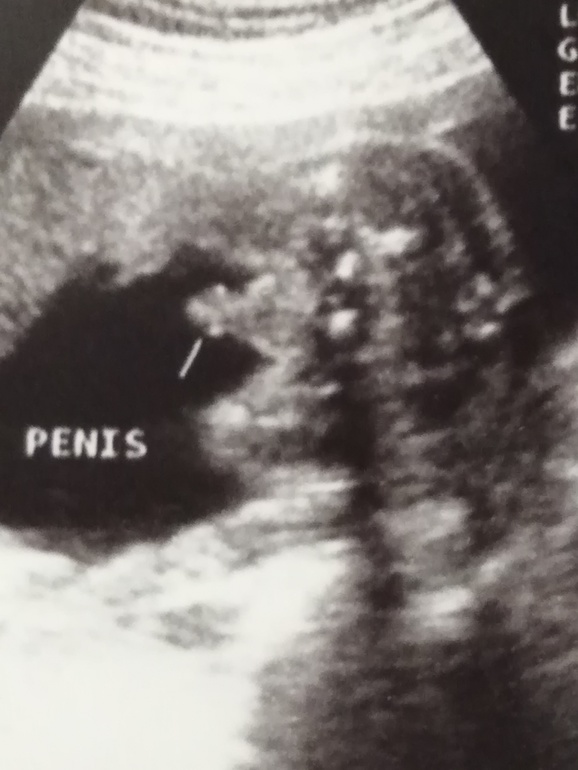

Кто что видит 😞? обведен писюн 😊.

И самое что настораживает что врач узист сказала что сомневается и написала 99%🤔странная какая то.

Мне тоже ваш снимок кажется неоднозначным)

Вот наш пенис в 22н5д))))

Не обманули)

А у вас неточно, как мне кажется)